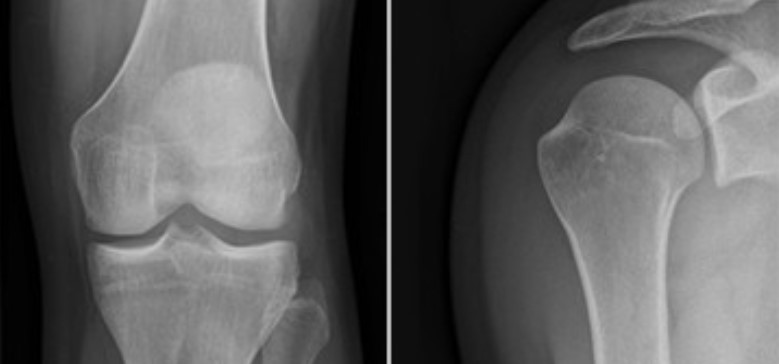

- Diagnostik: Präzise Bildgebung von Bewegungsapparat, Knochen, Gelenken und Weichteilen mittels MRT, CT und Röntgen.